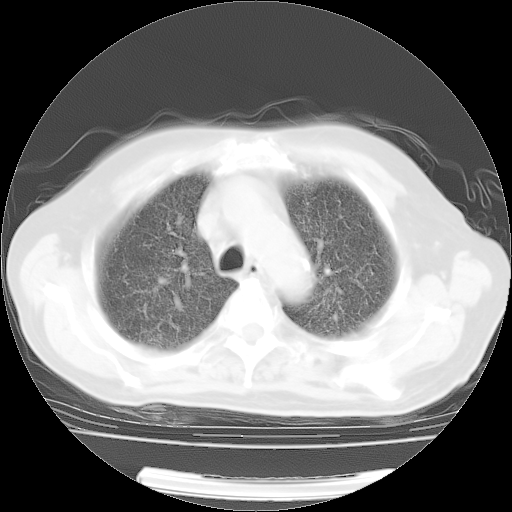

肺部CT平扫未见异常。

4月14日肺部CT